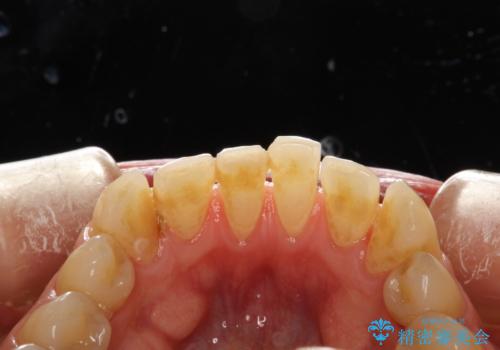

矯正治療終了後にPMTC(Professional Mechanical Tooth Cleaning)

担当医 歯科衛生士